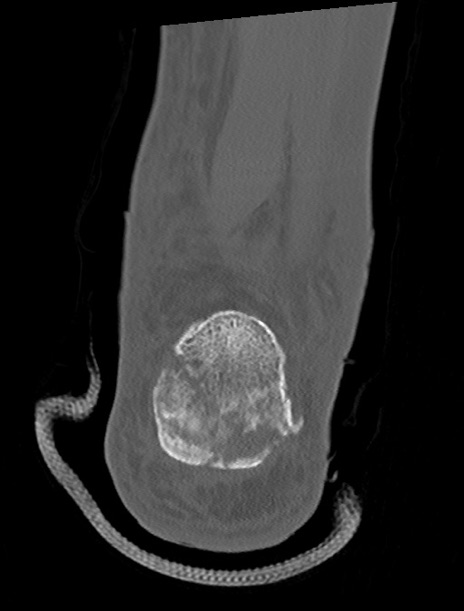

症例37 左足関節CT(冠状断像)

左足関節CT

矢状断像